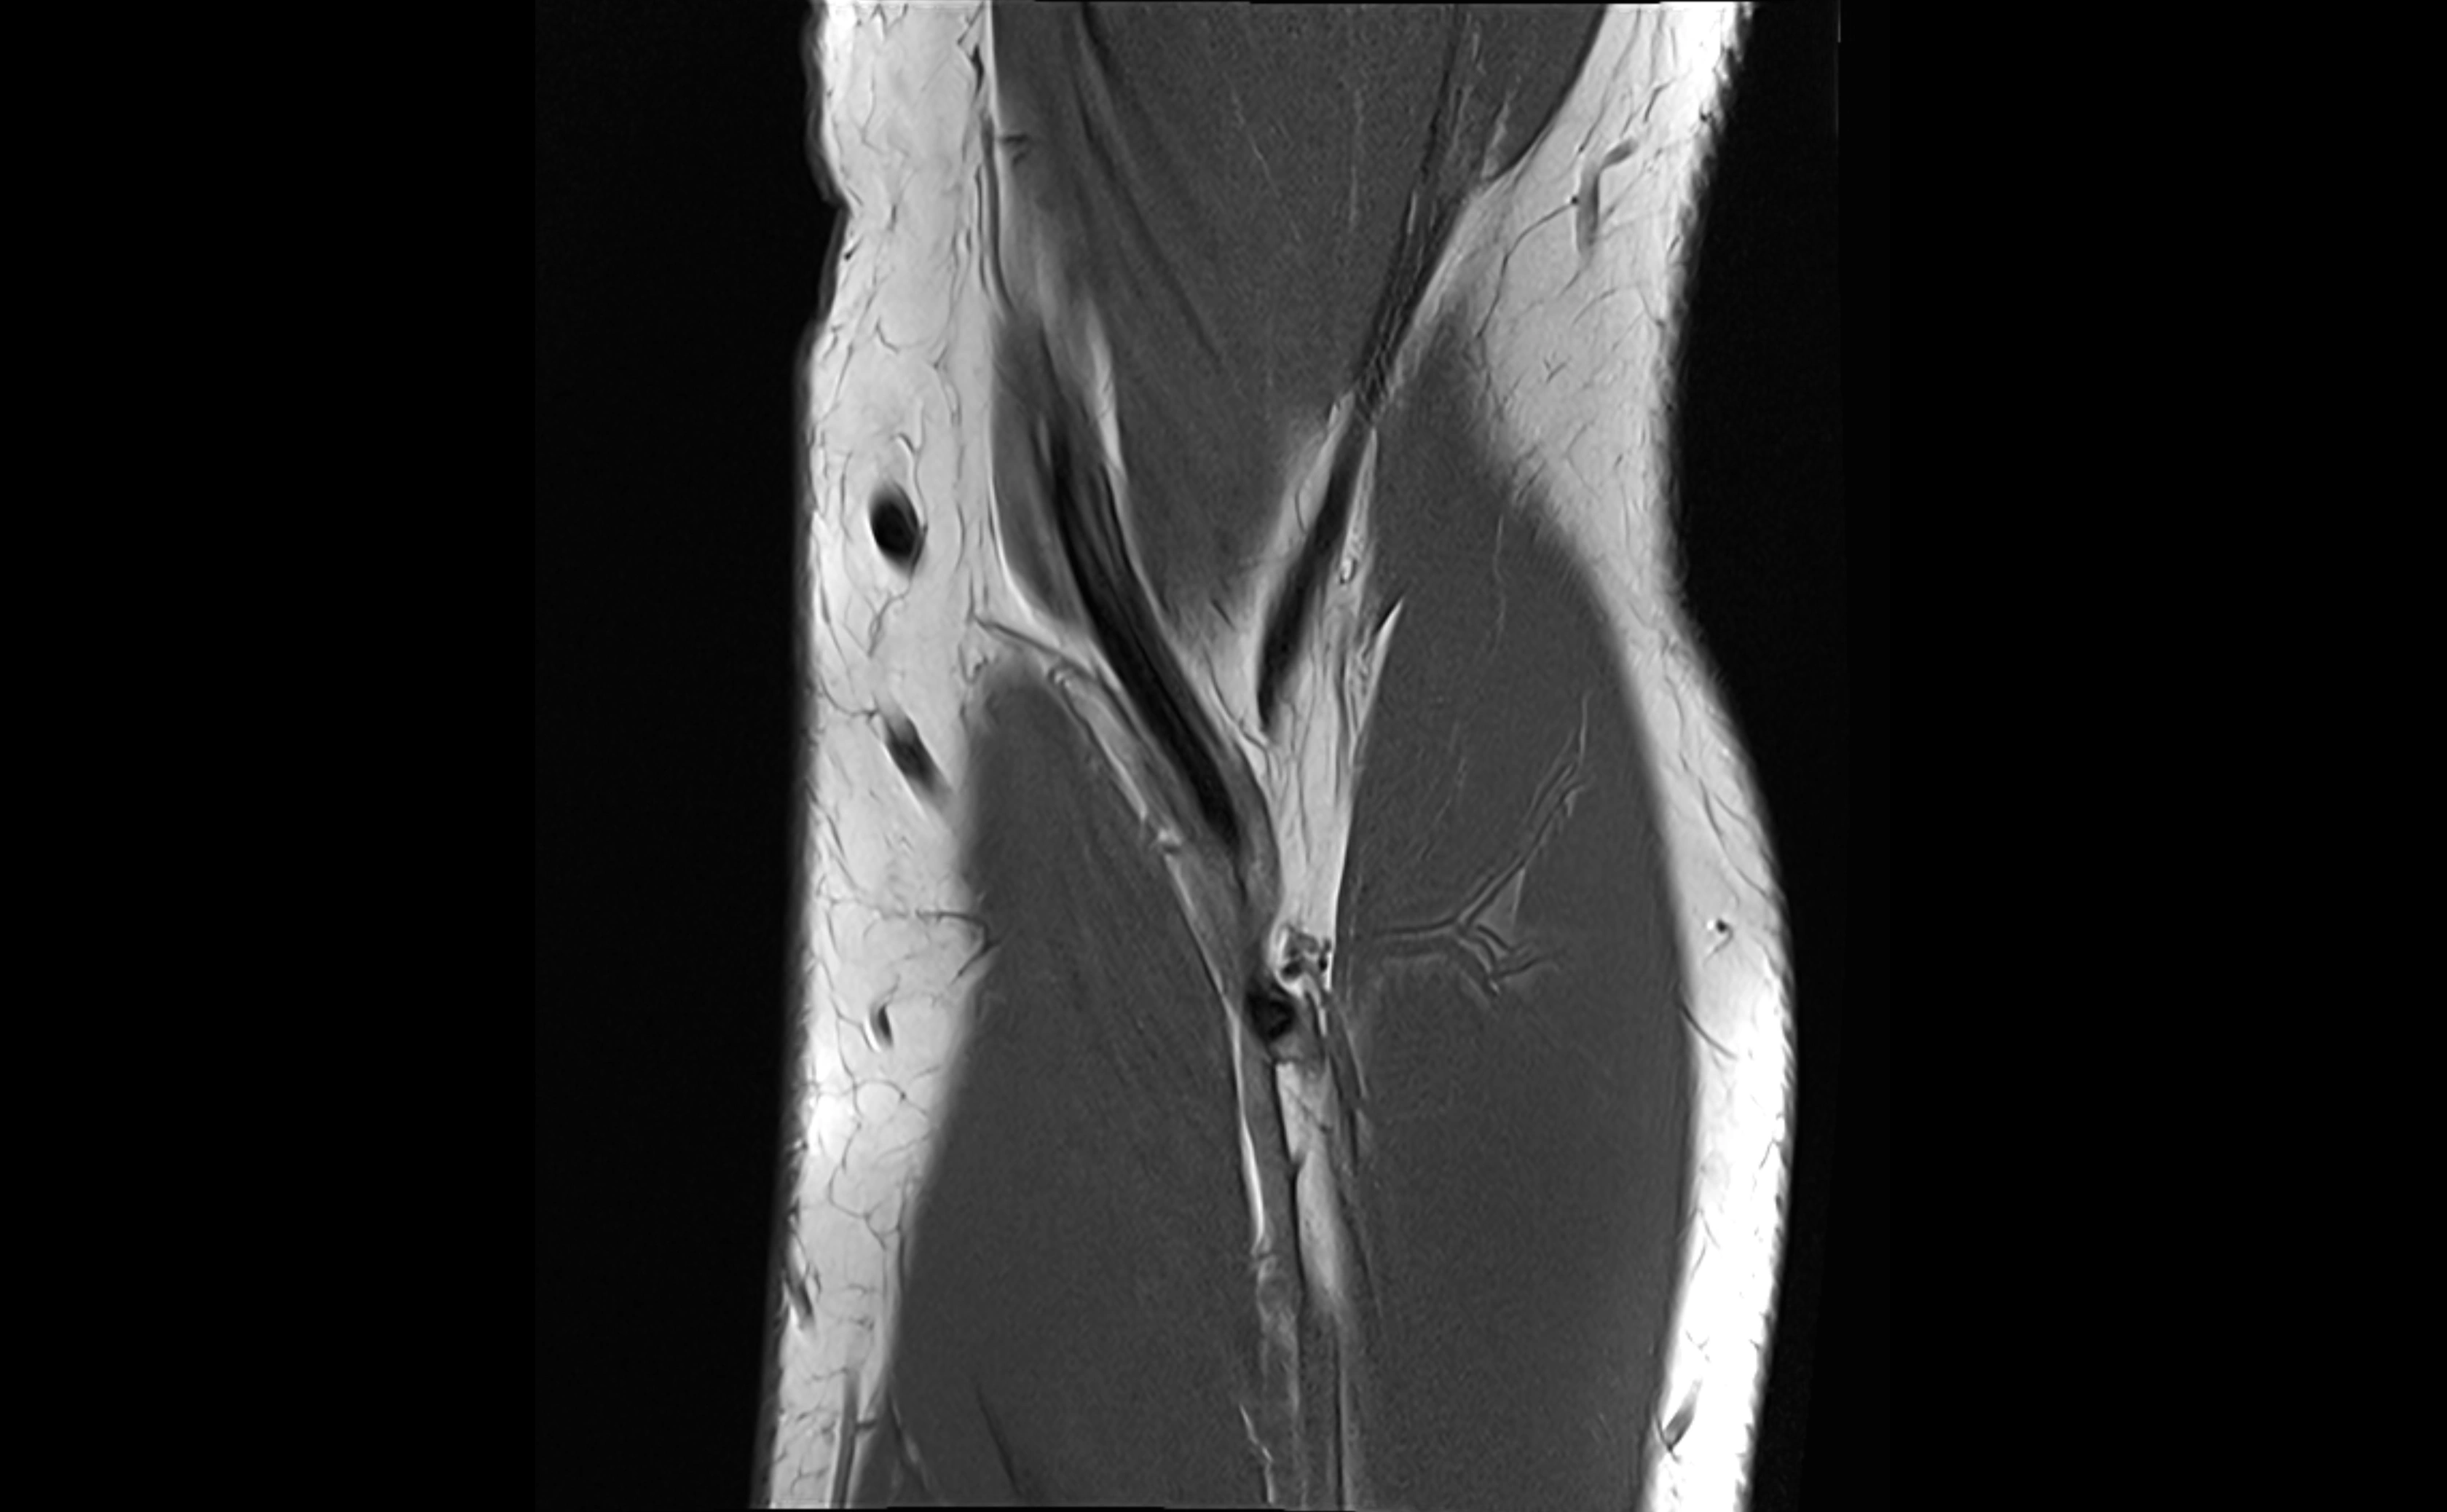

MRI images

image